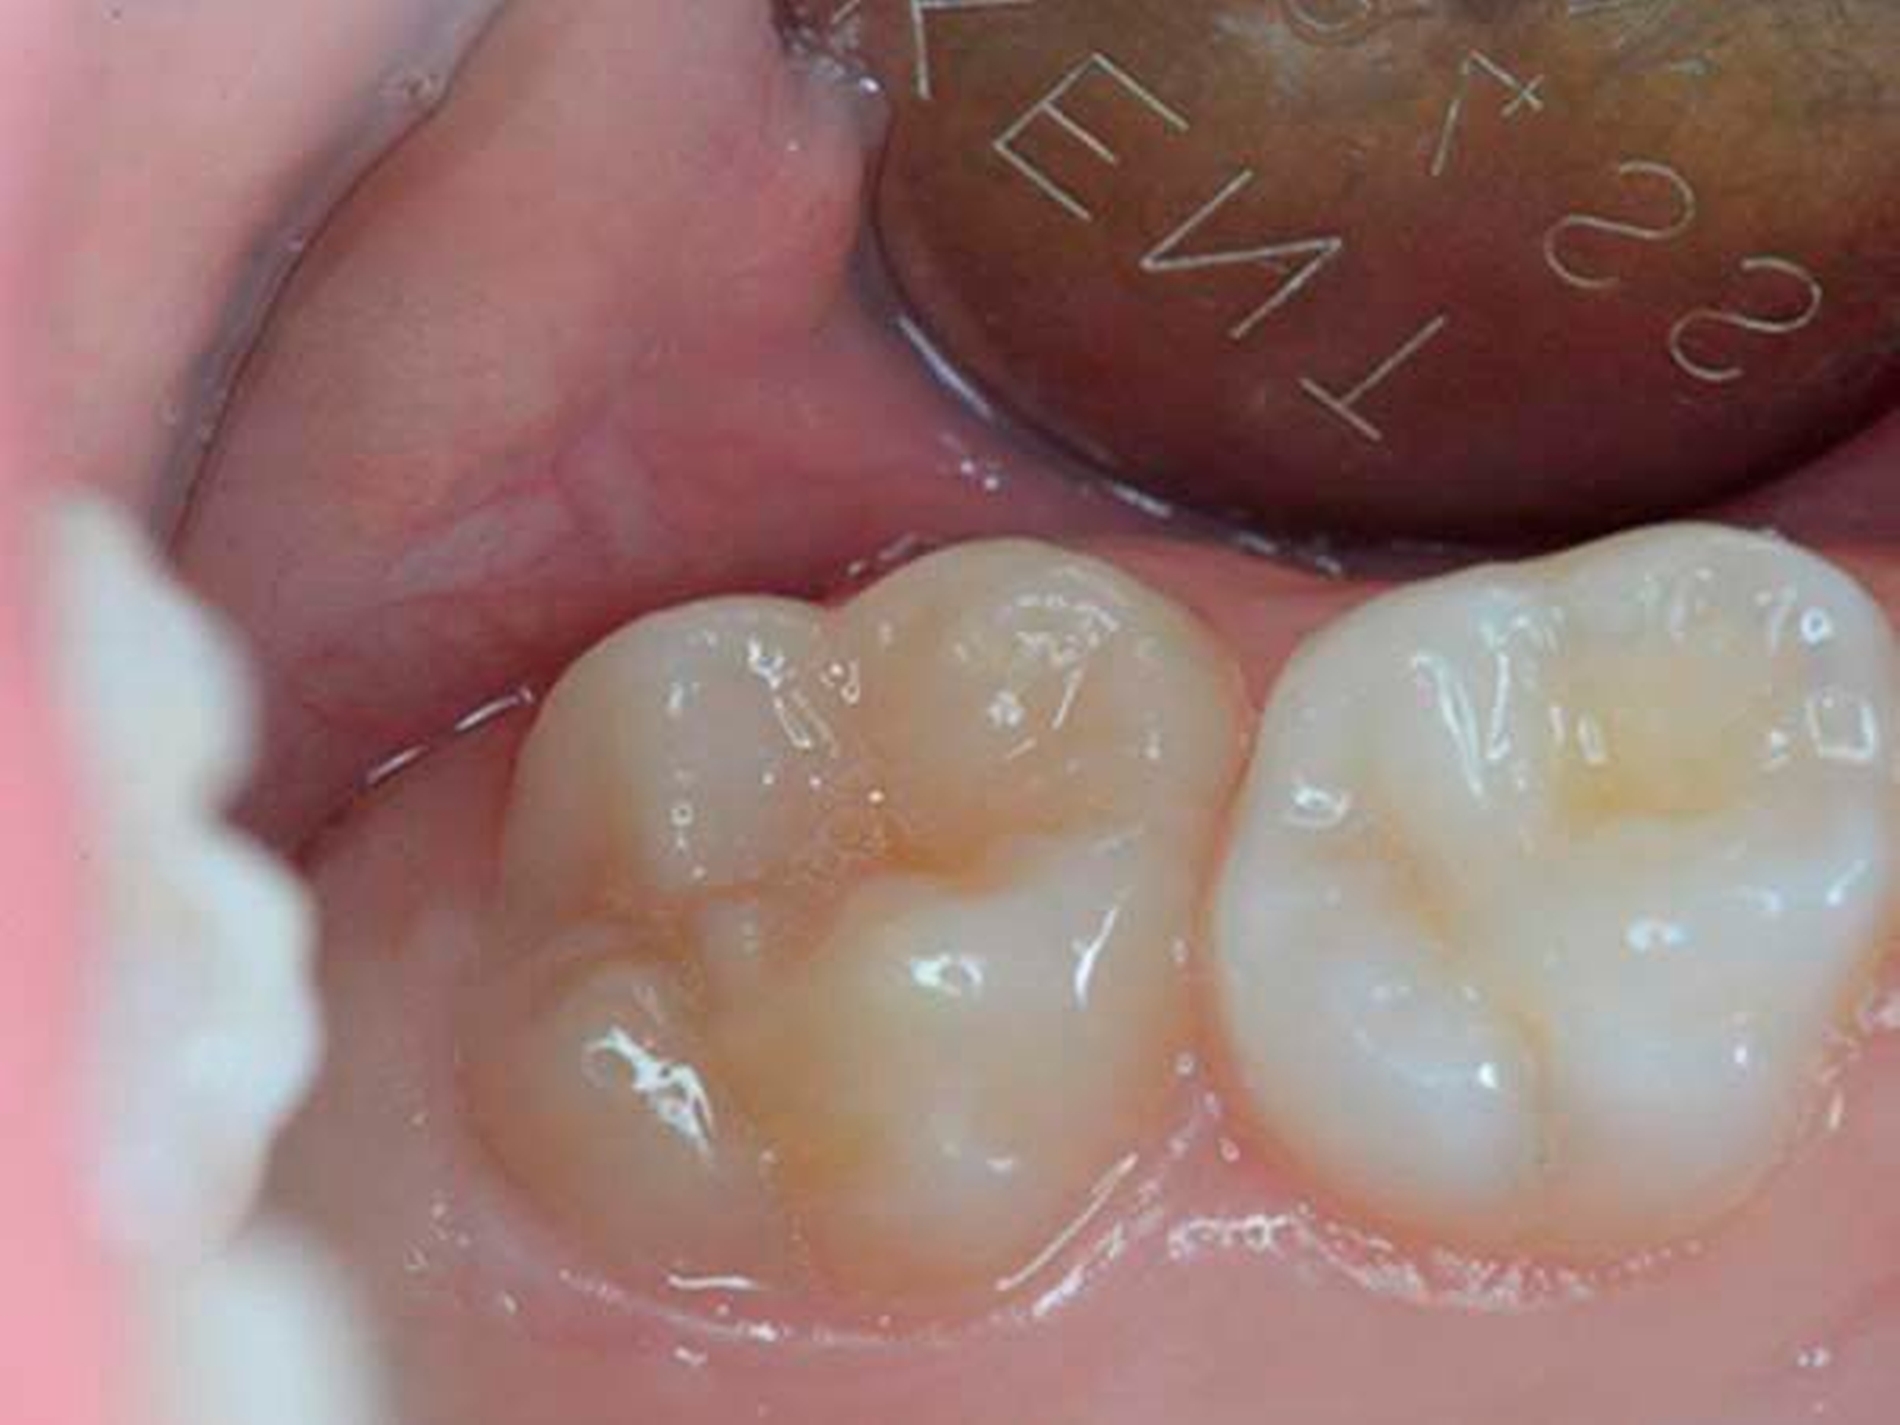

Verschiedene Theorien, wie zum Beispiel eine Antibiotikagabe während der Schwangerschaft, Bisphenol-A-Belastungen, Dioxine und Furane aus der Umwelt, ein bestehender Vitamin-D-Mangel und auch Infektionen mit Windpocken wurden als Ursache dafür diskutiert, dass Kinderzähne - vorwiegend die Sechsjahrmolaren oder die Schneidezähne - sich nicht normal entwickeln, sondern dass der Schmelz weich oder gar bröckelig ist und dem Zahn keinen Schutz bietet. Diese Zähne sind dann sehr empfindlich, die Kinder haben Schmerzen und die Zahnärzte ein Problem. Das Aufmacherbild zeigt einen zehnjährigen Patienten: Zahn 26 ist deutlich verfärbt mit hypomineralisierter Zentralfissur.